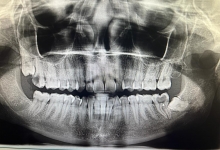

Clinica LUY ESTHETIC ART defineste parodontoza ca fiind rezultatul direct al placii dentare, care se depune pe suprafata dintilor, dar si in apropiere de marginea gingivala. Aceasta boala duce la pierderea dintilor, chiar daca ei sunt aparent sanatosi si nu prezinta carii. Edentatiile, afecteaza vorbirea, aspectul, dar si capacitatea de a mesteca.

Boala parodontala are un caracter progresiv. Pentru cazurile mai grave, recomandam tratamentul parodontal chirurgical rezectiv sau regenerativ.